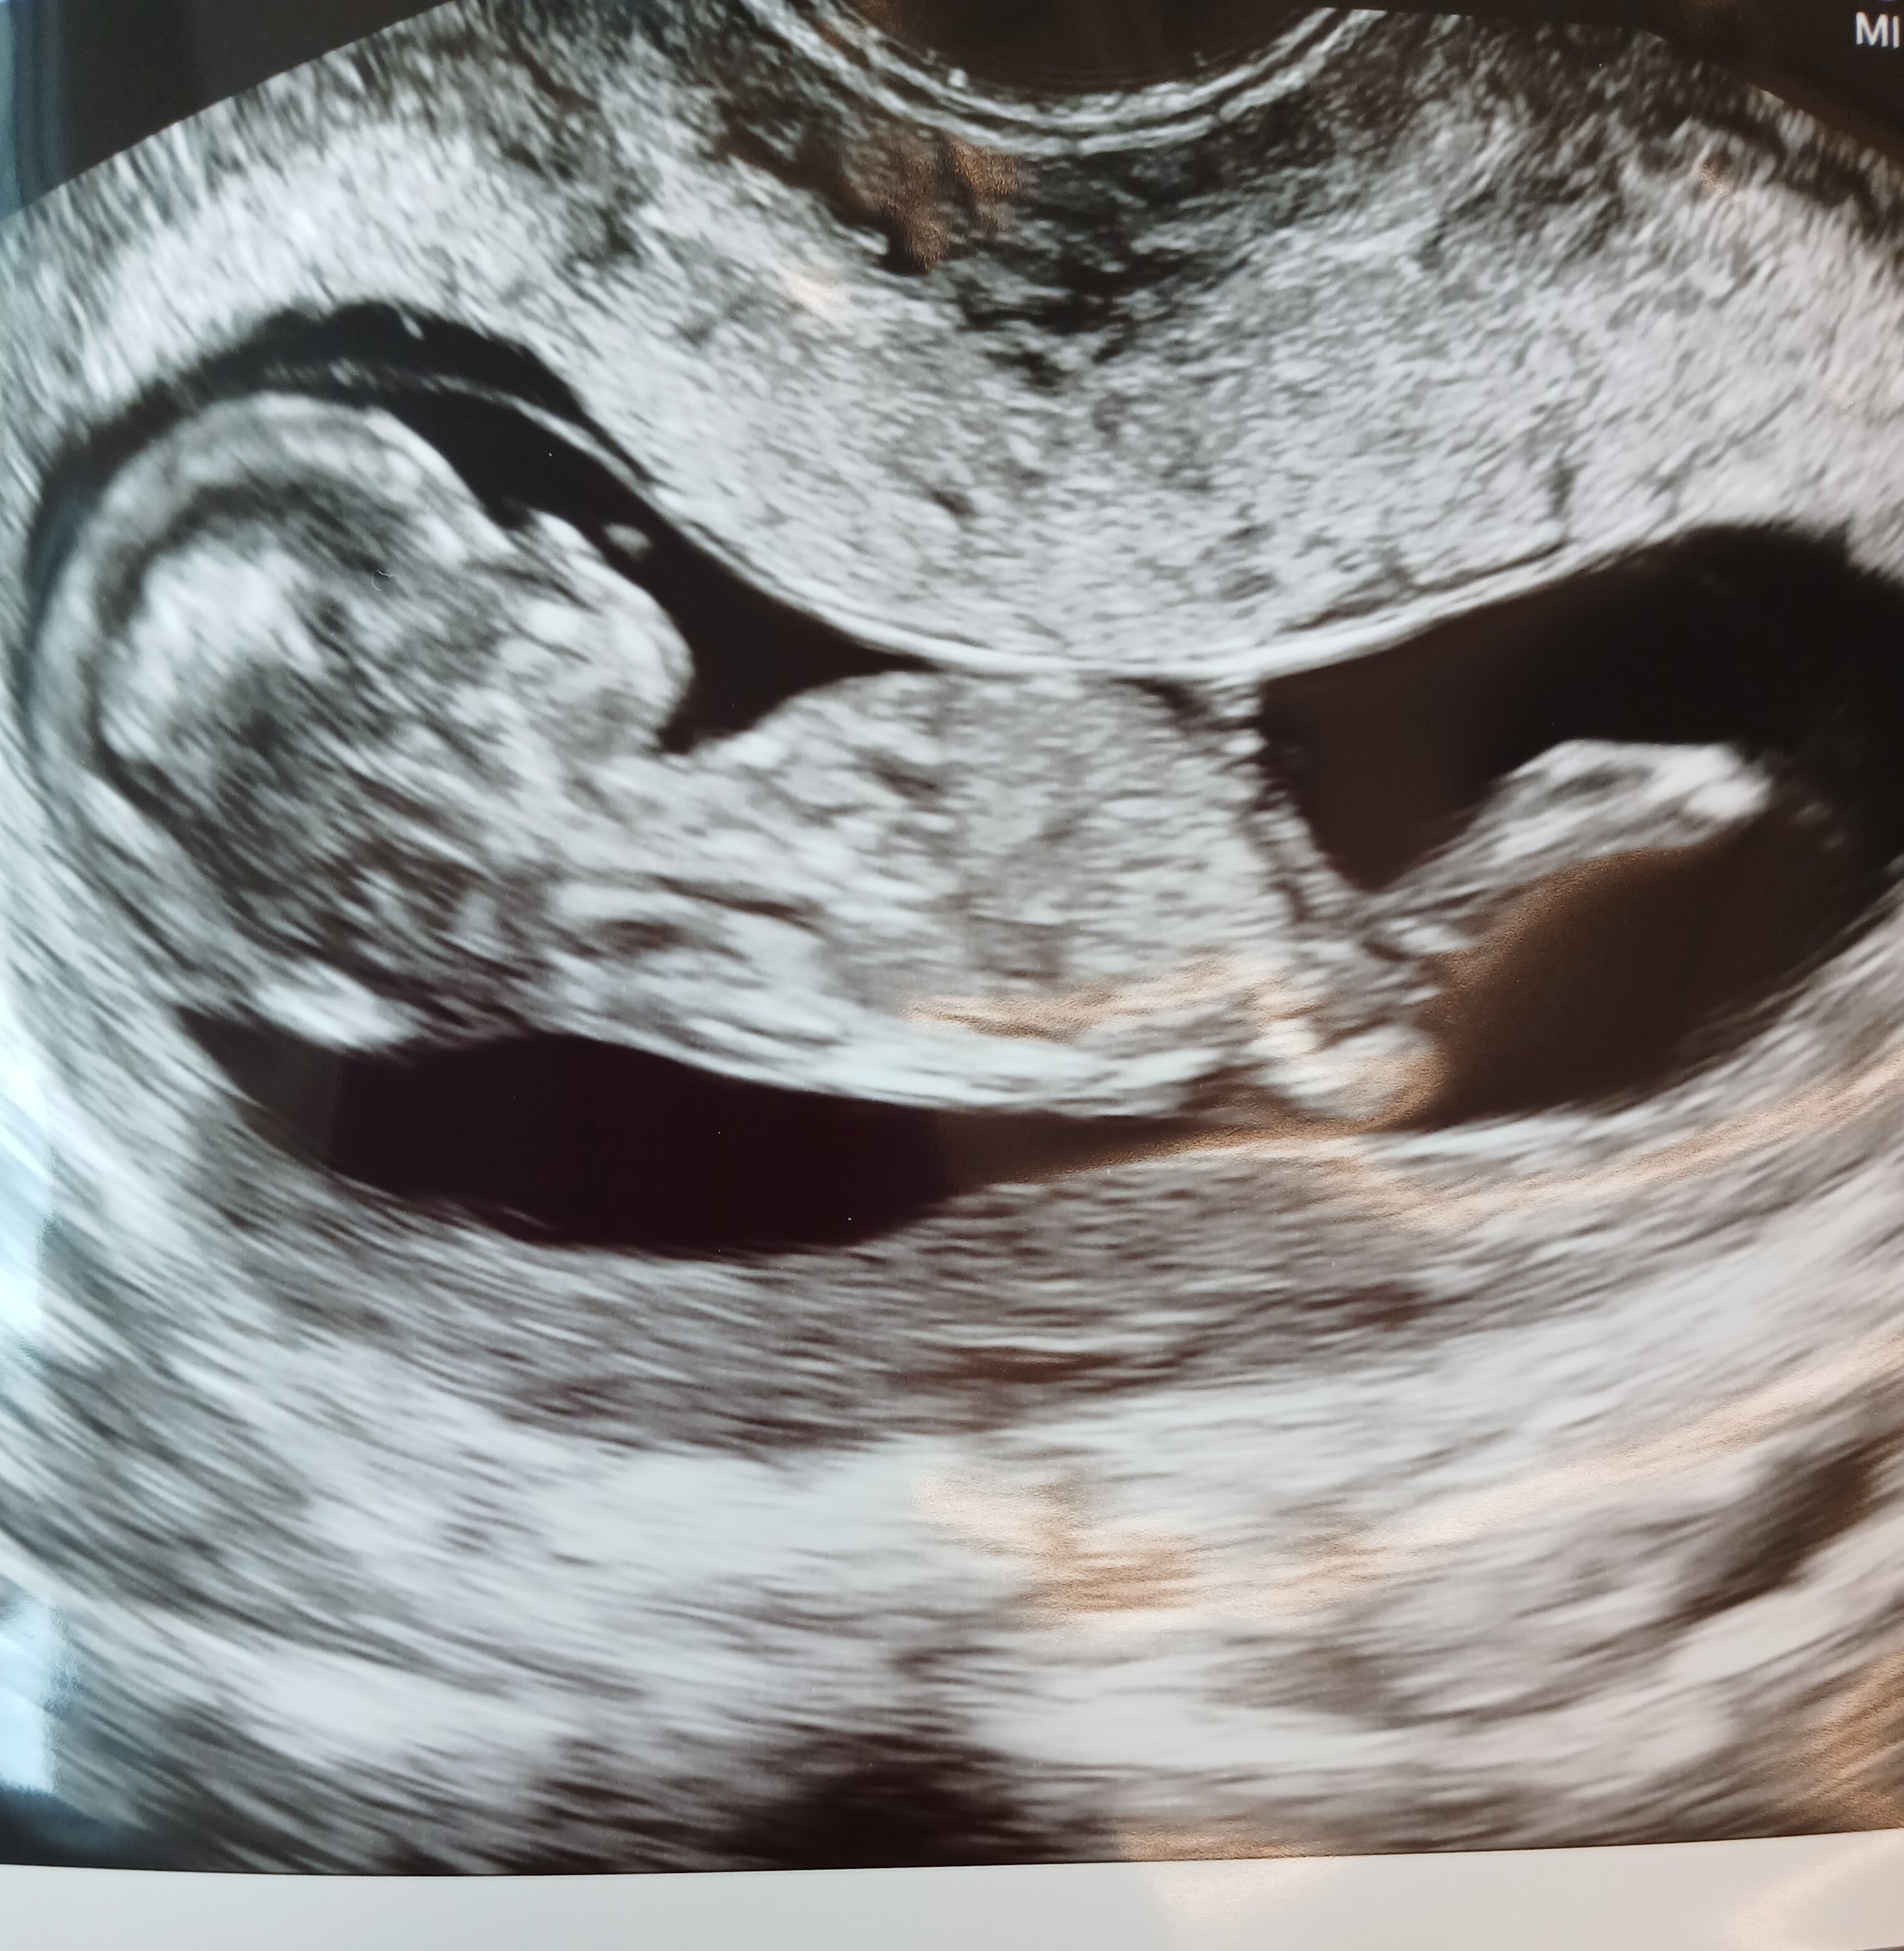

Kyllä tää kovasti tytöltä näyttää…Olisi myös tämä kuva

Tässä ei näy nubia.